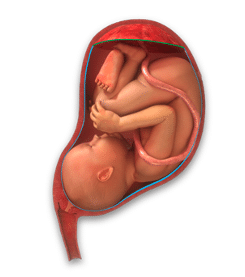

Omnigen Tereo processed amniotic membrane, is a patented dry preparation of human amniotic membrane. Amniotic membrane is the innermost layer of the placental sac, which protects and holds the foetus during pregnancy. NuVision upcycles and transforms this waste product of birth into an effective wound care product. The Tereo manufacturing process, developed at the University of Nottingham’s Academic Ophthalmology department, transforms this waste product of birth into a sterile and stable dry regenerative therapy that can be easily shipped and accessed anywhere in the world. Omnigen is applied directly to the wound dry and is rapidly and effectively rehydrated using surrounding moisture to immediately reactivate the beneficial properties to promote tissue repair and healing in a variety of ways. The product represents a unique and versatile “off-the-shelf” regenerative product, and it may be stored long-term. The Tereo process preserves the wound healing action and provides surgeons with an effective sight saving therapy that could provide a meaningful benefit to patients, including those suffering from ocular surface disease and conditions with unmet medical need.